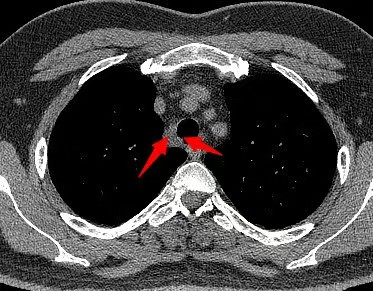

患者为35岁男性,在体检中发现上纵隔气管旁存在一直径约1.5厘米的肿物。胸外科为其进行了超声支气管镜引导下经支气管针吸活检术,病理结果提示为神经鞘瘤。影像学检查显示肿物疑似侵犯气管,但气管镜观察见局部黏膜尚光滑、仅略有隆起,病情具有一定复杂性。